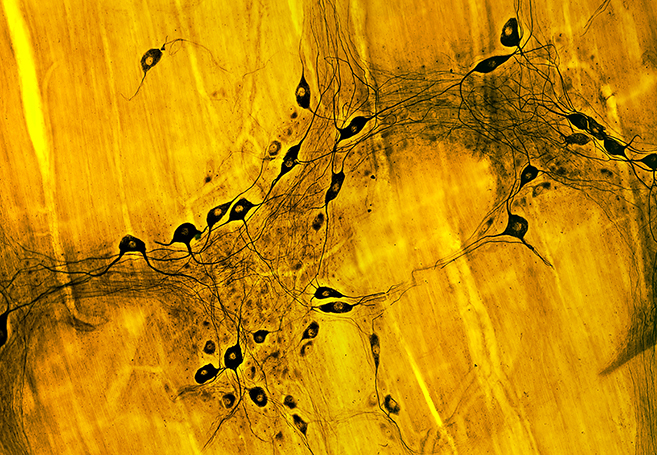

Parkinson’s emerges from the death of neurons deep in the brain, and the death of these neurons leads to stiffness, shakiness, tremors, and difficulty moving. Although there are drugs available which can help alleviate the symptoms, they become almost useless as the disease gets worse and worse. The neurological red flag of Parkinson’s involves synuclein molecules — typically harmless insoluble fibers in healthy nerve cells, which for some reason in people with Parkinson’s, begin to twist, contort, and clump together to form problematic fibers.

About 10 years ago researchers began to suspect that Parkinson’s starts somewhere other than the brain. They discovered the signature synuclein fibers in the gut during autopsies — in the guts of people who had full blown Parkinson’s (i.e. fibers in the brain as well), and in people who hadn’t yet developed symptoms of Parkinson’s (yet still had early stage fibers in their brains). The trigger is suspected to be some sort of toxin or microbe.

Now researchers at the California Institute of Technology have observed the gut-to-brain spread of synuclein fibers in mice. Three weeks after the mice had these fibers injected into their stomachs, the fibers were then found in the area of the brain that governs movement, and the mice began to show the hallmark symptoms of Parkinson’s.

Image source: Microscape/Science Photo Library via New Scientist